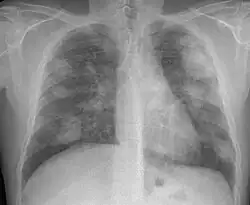

Complicated silicosis -

- Complicated silicosis

- Silicosis can become "complicated" by the development of severe scarring (progressive massive fibrosis, or also known as conglomerate silicosis), where the small nodules gradually become confluent, reaching a size of 1 cm or greater. PMF is associated with more severe symptoms and respiratory impairment than simple disease. Silicosis can also be complicated by other lung disease, such as tuberculosis, non-tuberculous mycobacterial infection, and fungal infection, certain autoimmune diseases, and lung cancer. Complicated silicosis is more common with accelerated silicosis than with the chronic variety.